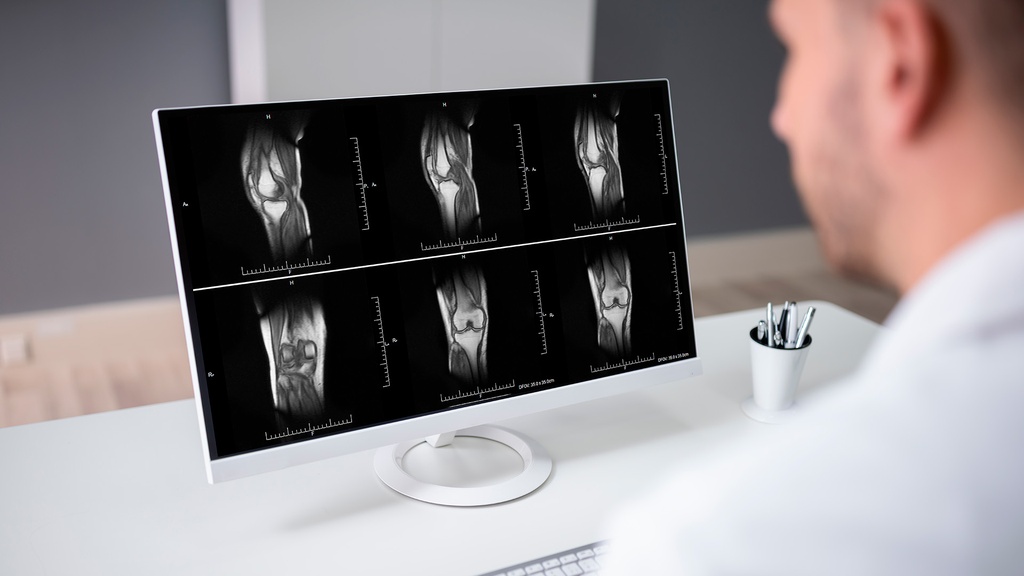

RM RODILLA DERECHA

Interpretación por especialista

Sí